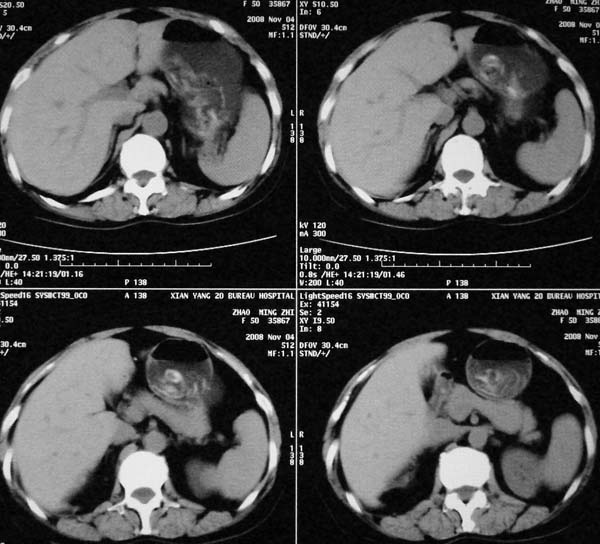

以下是引用dr.yang在2008-11-9 21:56:00的发言:[br]右肾上极占位?建议增强

以下是引用x-man在2008-11-9 22:30:00的发言:[br]建议先增强,右肾影明显增大,上极见边不清低密度肿块影,肿瘤待定.

以下是引用卜一在2008-11-10 8:09:00的发言:[br]建议先增强,右肾影明显增大,上极见边不清低密度肿块影,肿瘤待定.支持!另:第一次碎石是否肾受到损伤?合并感染?不知第一次碎石前是否做过彩超?

以下是引用dsl555在2008-11-9 23:57:00的发言:[br]建议先增强,右肾影明显增大,上极见边不清低密度肿块影,肿瘤待定. [br] [br]